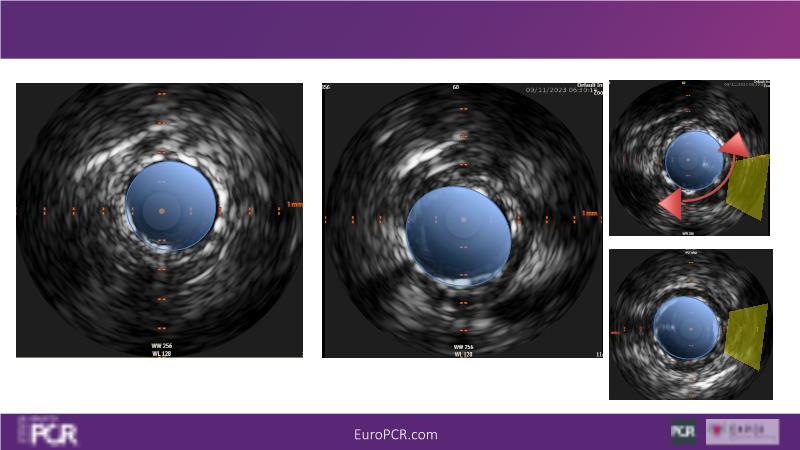

Join this session to delve into the unmet needs concerning drug-eluting stents (DES), including poor long-term clinical outcomes, with up to a 50% MACE rate at 10 years, and a non-plateauing 2-3% annual event rate. Explore how DynamX Bioadaptor technology addresses these challenges by maintaining the established flow lumen and restoring hemodynamic modulation of the artery. Discover the sustained clinical benefits demonstrated in a 2-year RCT, potentially establishing a new treatment standard for CAD patients. Gain insights into patient types benefiting most in clinical practice, such as those at higher risk of restenosis (e.g., LAD disease, long lesions, small vessels, co-morbidities), and younger patients with longer lifespans.

- To understand the unique design characteristics of Bioadaptor, the connection between biology of atherosclerosis and restoration of vessel physiology and function